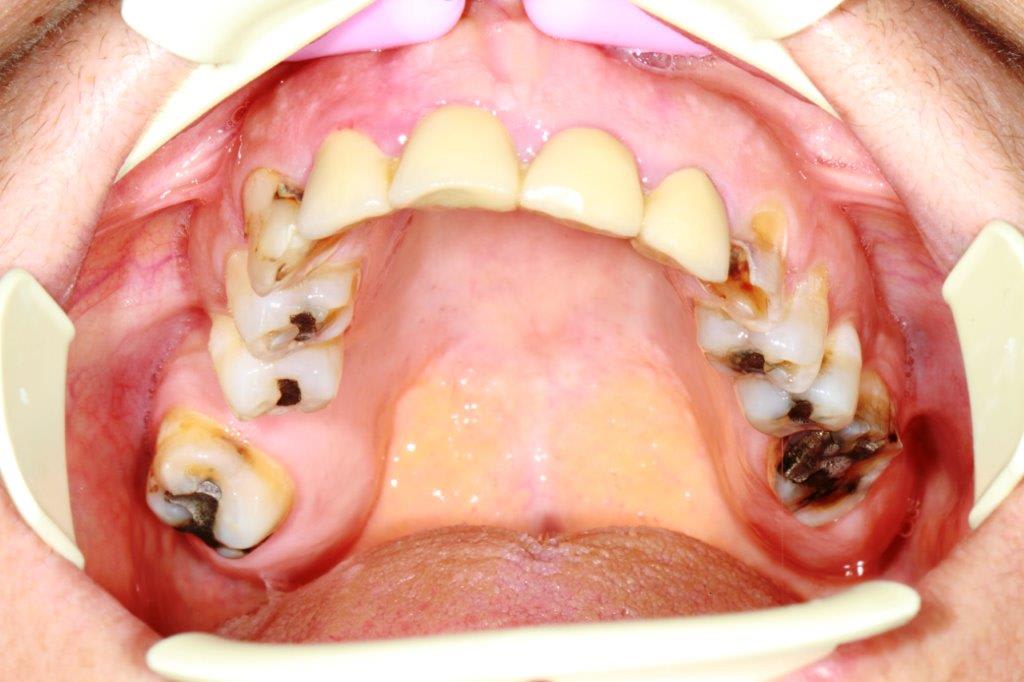

Non je ne croyais pas que ce cas se ferait, et la patiente vient de decider...donc empreintes et réflexions.

Devis accepté acompte versé il me reste a trouver la solution.

À priori travail sur dents vivantes sauf celles qui sont. Déjà traitées dv légèrement modifiée,et retablir une occlusion standard...un peu chaud quand même.

Pas d'implant prévu ni ortho

On va faire chauffer l'Emax....

Je regardais comment retrouver le plan d'occlusion, je tirerais ma plaque de fox depuis les pointes canines mandibulaires, provisoires en postérieur, puis provisoires en postérieur maxillaire à la hauteur qui te convient, dans la même séance. Je laisse la béance antérieure créée jusqu'à la prochaine, elle devrait déjà se sentir un peu plus relax.

Séance suivante, horizontalisation (on n'a pas les repères du visage) de la ligne incisive mandibulaire, provisoires devant au maxillaire. Ca devrait permettre d'y voir plus clair.

sur ce cas , il y a 1 truc de particulier ,,ç est que les dents de devant sont solidarisées ( d'apres la pano )

ce qui voudrait dire que lorsque le bridge a été fait ,il y avait déjà la compensation osseuse et l'occlusion croisée .

ceci me fait réfléchir, j'ai tendance à commencer par le maxillaire, car il est fixe dans l'espace, contrairement à la mandibule qui porte avec elle les défauts d'occlusions, latéro-déviation etc...accumulées pendant de nombreuses années, néanmoins ceci n'est pas forcement figé dans mon esprit, donc éventuellement....